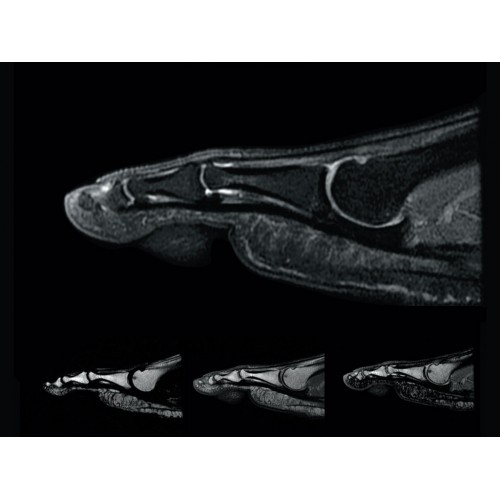

• РЧ-катушки, оптимизированные для исследования конкретных участков тела — элементы катушек высокой плотности располагаются вокруг исследуемых участков тела и при необходимости обеспечивают расширенный охват и оптимальное качество изображений при каждой процедуре.

• Широкое поле зрения — поле зрения шириной 50 см позволяет охватывать крупные анатомические области за меньшее число сканов.

• Непревзойденные возможности по визуализации молочных желез — благодаря приложениям IDEAL и VIBRANT-FLEX ни один сравнимый МР-томограф не способен так хорошо захватывать такие большие участки тела.